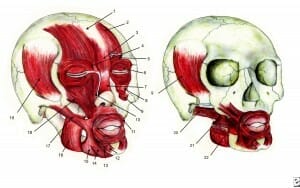

Mediale pterygoideus

De mediale pterygoideus bevindt zich aan de zijkant van...

Lees Meer +

Masseter

De masseter bevindt zich aan de zijkant van de kaak. Hi...

Lees Meer +